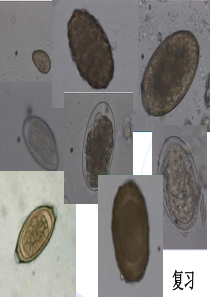

82寄生虫